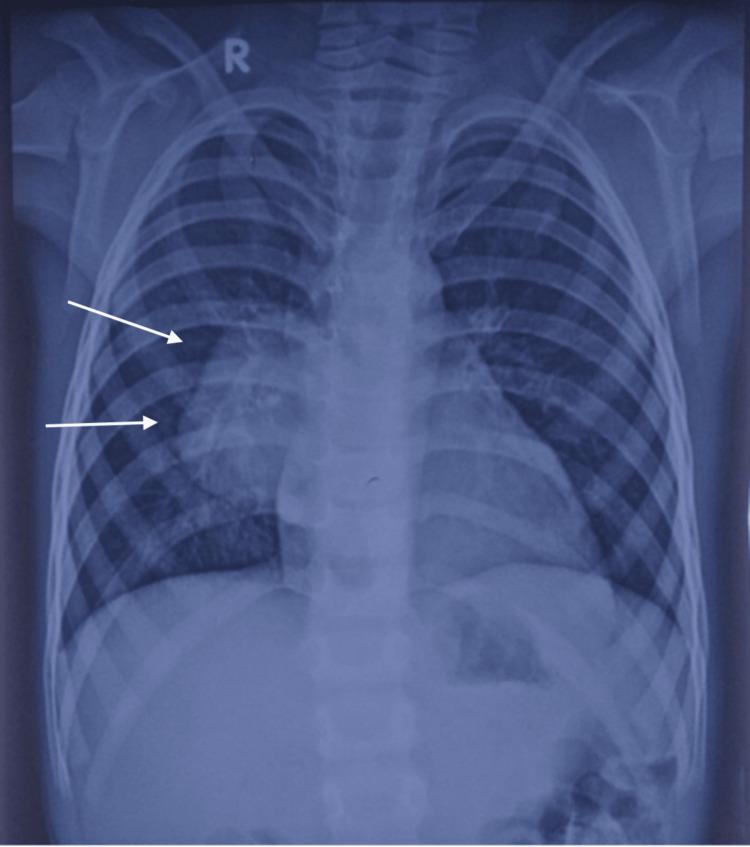

The pulmonary artery-to-left atrium (LA) fistula is one of the rare and unique structural causes of silent cyanosis. This correctable abnormality can be identified by having a high index of clinical suspicion and appropriate investigations using echocardiography and cardiac computed tomography (CT). We report an eight-year-old child who had worsening exertional dyspnea, long-standing central cyanosis, and recurrent infections. A large-sized fistula connecting the right pulmonary artery (RPA) to the LA with all the right- and left-sided pulmonary veins showed normal drainage into the LA, suggesting a type I RPA-to-LA fistula, which was diagnosed on cardiac CT. Percutaneous closure using the occluder device is planned as further management for the patient.

肺动脉至左心房瘘是导致隐匿性发绀的罕见且独特的结构性病因之一。这种可纠正的异常情况可通过高度的临床怀疑指数以及使用超声心动图和心脏计算机断层扫描(CT)进行适当检查来识别。我们报告一名8岁儿童,其劳力性呼吸困难加重、长期中心性发绀且反复感染。一个连接右肺动脉(RPA)与左心房的大型瘘管,所有左右肺静脉均正常引流至左心房,提示为I型RPA至左心房瘘,这是通过心脏CT诊断出来的。计划使用封堵器进行经皮封堵作为该患者的进一步治疗措施。